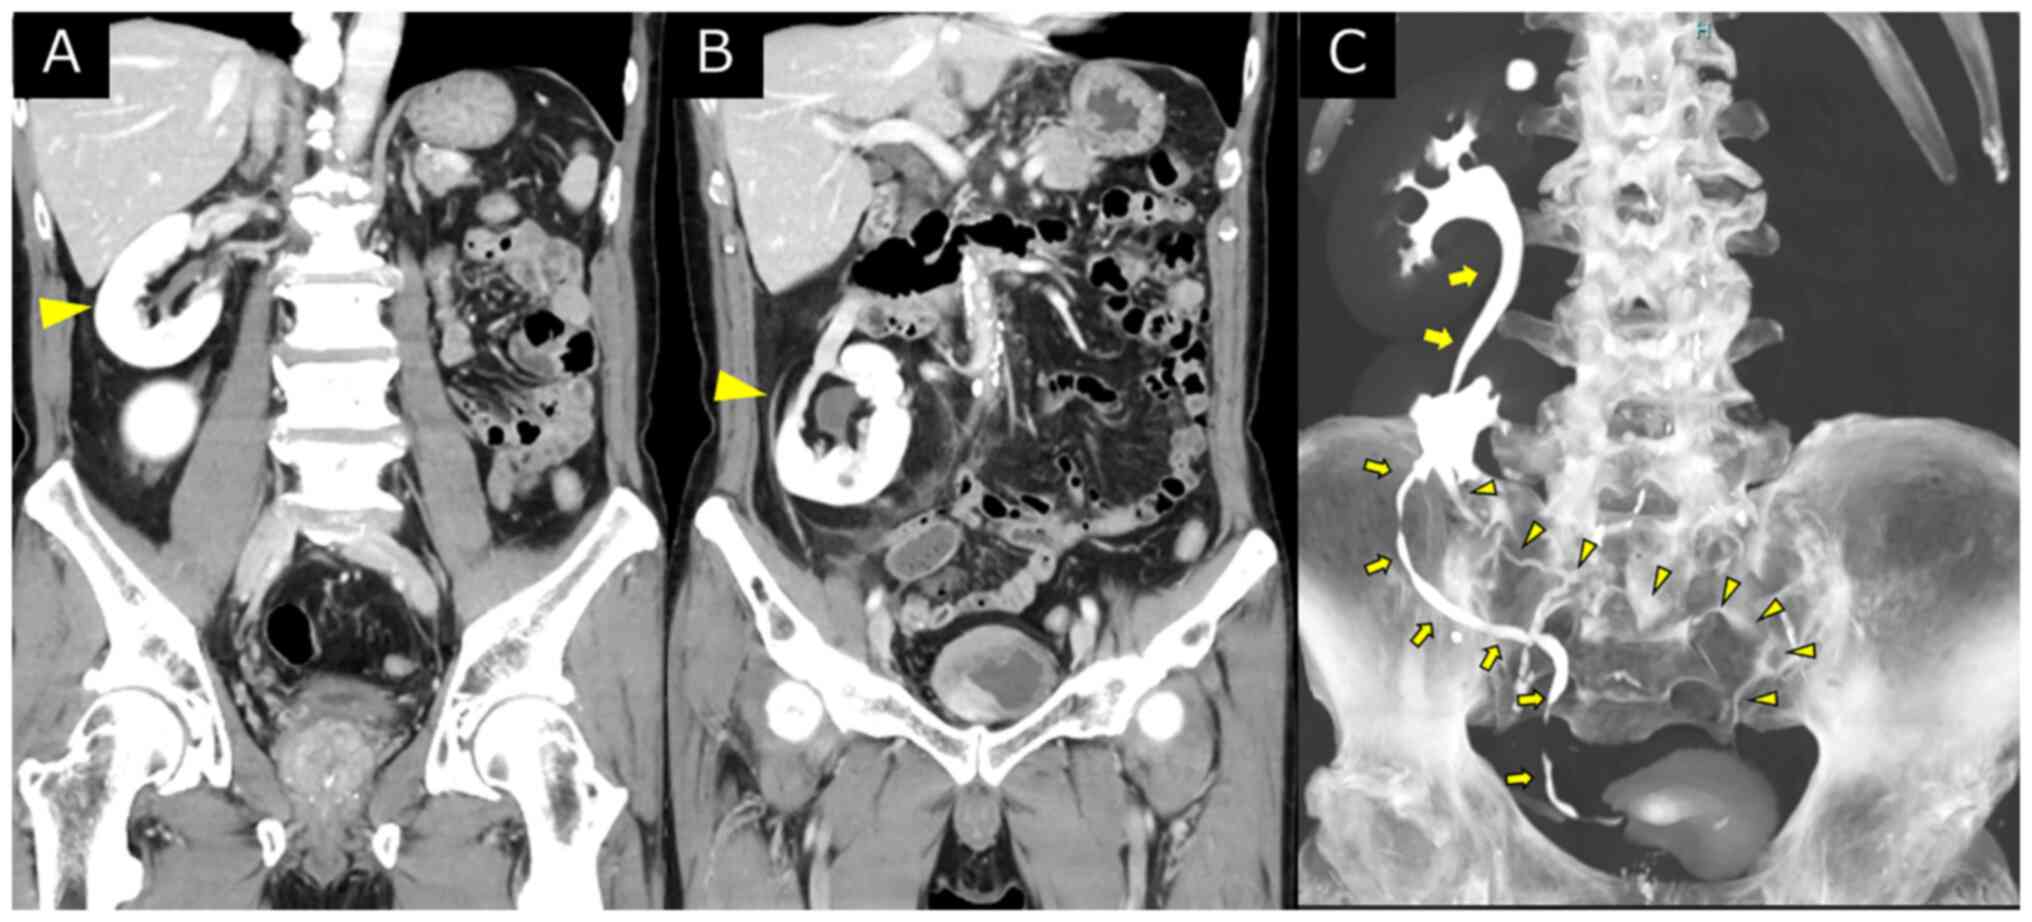

Feasibility of robot‑assisted radical cystectomy in a patient with an ectopic kidney: A case report

An ectopic kidney is a rare congenital defect in which the kidney does not migrate to its normal anatomical position. In the present study, a robot‑assisted radical cystectomy and intracorporeal urinary diversion were performed for a patient with an ectopic kidney. The present study describes the case of a 72‑year‑old male patient who was diagnosed with a bladder tumor by magnetic resonance imaging and cystoscopy. A transurethral resection of the bladder tumor was performed. The pathological examination revealed an invasive urothelial carcinoma. Contrast‑enhanced computed tomography revealed an ectopic left kidney in the upper pelvis. A robot‑assisted radical cystectomy, extended lymph node dissection and intracorporeal urinary diversion were performed. On the whole, as demonstrated herein, a robot‑assisted radical cystectomy with intracorporeal urinary diversion is a feasible approach for muscle‑invasive bladder cancer complicated by an ectopic kidney.